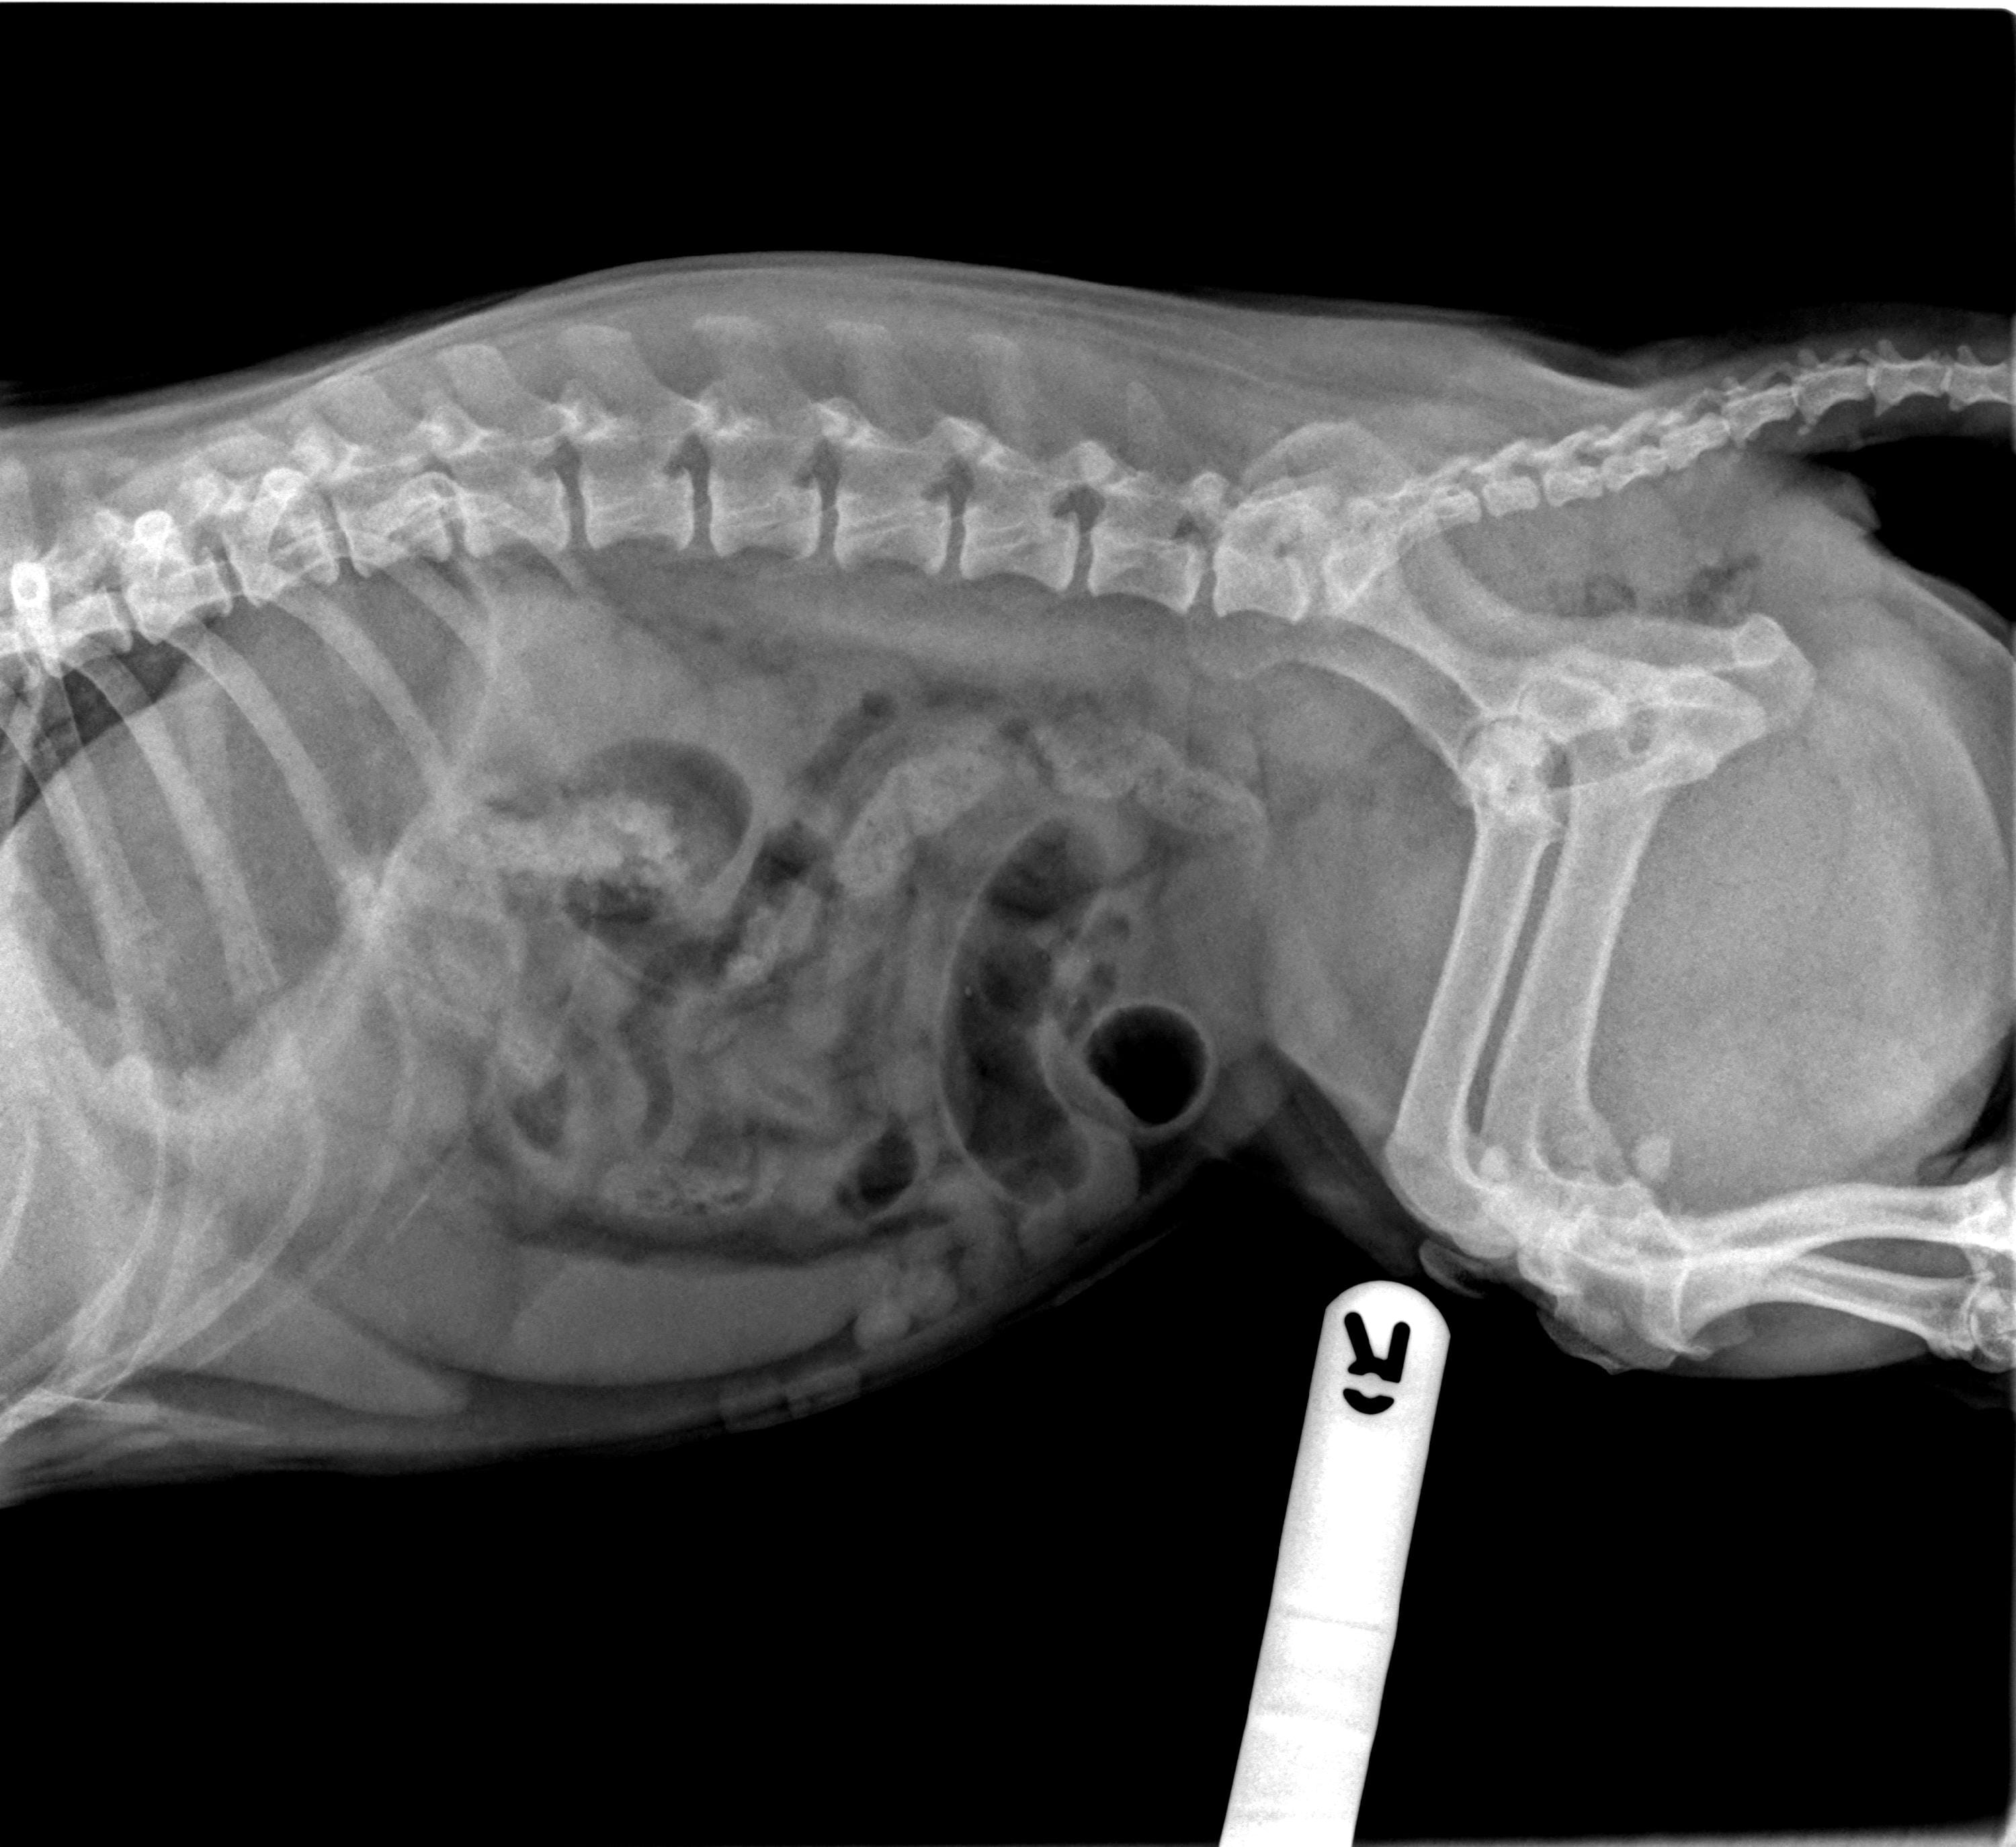

Proximal duodenal and gastric outflow obstruction can cause persistent vomiting with low serum Na, Cl and K; these electrolyte changes should be considered very suspicious even in the absence of imaging findings for obstruction. Abdominal radiographs should include orthogonal views (a right lateral and a ventro-dorsal or dorso-ventral image). Classic radiographic signs for surgical disease can include the “double bubble” for GDV ( Figure 1), two distinct populations of small intestine with obstruction (small and large diameter gut evident with, for example, intussusception, intestinal mass or foreign body; Figure 2) or free abdominal gas with a lack of serosal detail with septic peritonitis. Free abdominal gas can be very obvious ( Figure 3) but a more subtle pneumoperitoneum is best recognised using a horizontal beam radiograph with the patient in lateral recumbency ( Figure 4). Of course, a lack of radiographic changes does not fully exclude a gastrointestinal emergency and abdominal ultrasound can help to identify the problem or guide further diagnostics (eg abdominocentesis of free abdominal fluid). Septic peritonitis due to intestinal leakage will result in an effusion with cytological identification of neutrophils and/or bacteria. If intracellular bacteria can’t be definitively identified but there remains a concern for septic peritonitis, glucose and lactate assessment can be helpful.